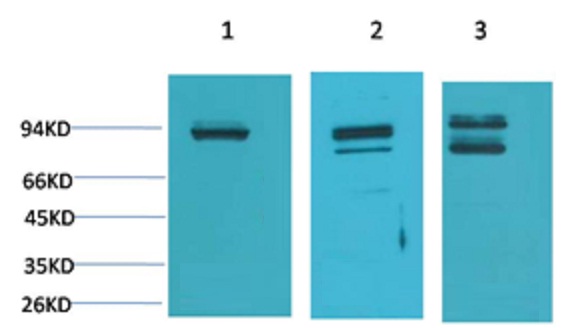

STAT1 Rabbit Polyclonal Antibody

Catalog NO.:BE3403

Applications :WB, IHC

Reactivity :H,R,M

| Recommended dilutions: | WB:1:1,000-2,000 IHC:1:200-500 |

| Specificity: | Antibody can detects endogenous STAT1 protein. |